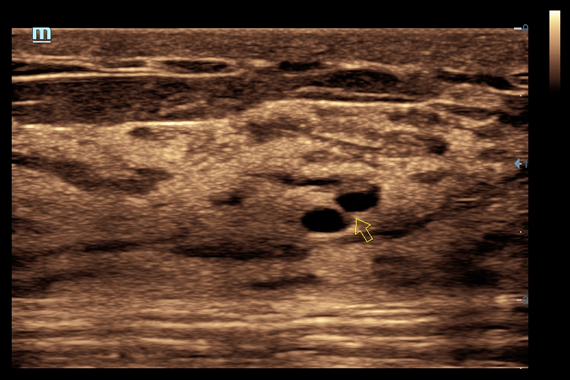

Система ультразвукового исследования Mindray DC-60 EXP X-INSIGHT является новейшей разработкой для проведения комплексных обследований на высшем уровне. Она обеспечивает решение самых сложных задач в таких областях, как кардиология, акушерство и гинекология, сосудистые заболевания, педиатрия и многие другие.

DC-60 EXP X-INSIGHT - это современный стационарный УЗИ-аппарат с функцией сенсорного управления и очищенной гармонической визуализацией, обеспечивающей лучшее контрастное разрешение и технологию 4D-визуализации. Он оснащен 21,5-дюймовым монитором, который может поворачиваться на 180 градусов, что удовлетворяет потребности врачей в качественной ультразвуковой диагностике.

• HR Flow - режим отображения кровотока с высоким временным и пространственным разрешением для точной и однородной визуализации сосудов, в том числе самых мелких.